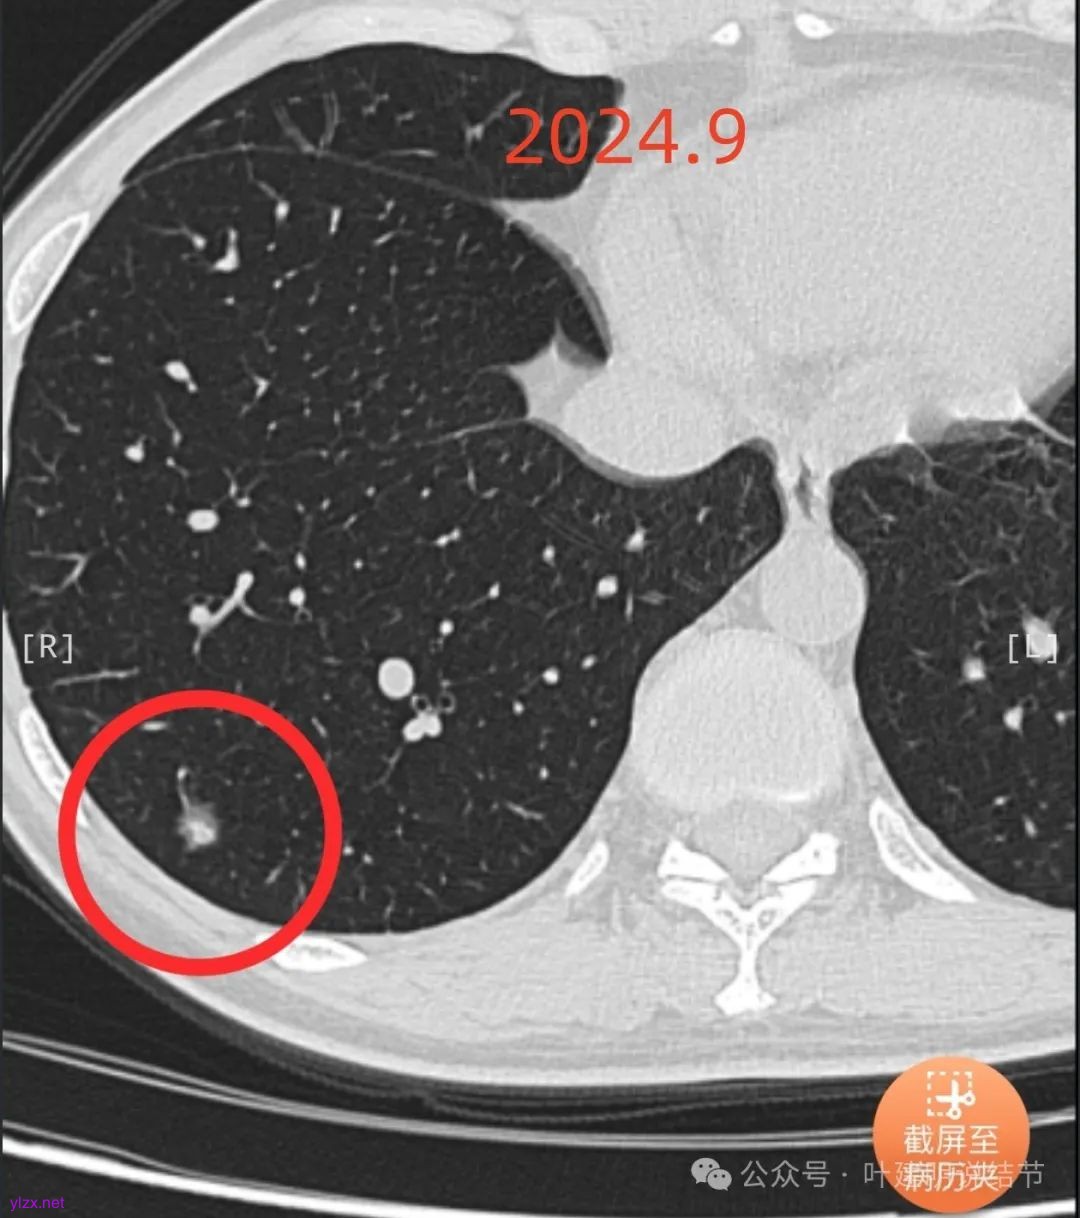

患者7年前在当地医院就诊时完善胸部CT发现肺结节,发现后未服用药物治疗,定期复查随诊,2024-09-29复查胸部CT提示:右肺下叶(薄234)见混杂密度小结节影,边缘毛糙,大小约0.8x0.7cm,其内见小血管穿行。双肺可见多发微小结节影,双肺见索条影,右肺可见小钙化灶。近期患者无咳嗽、咳痰、咯血、胸闷、胸痛、心慌、气急、头晕、头痛、畏寒、发热等不适,精神、饮食、睡眠正常,大小便正常,体重无明显变化。

2024年9月时病灶较前有所增大,实性成分增大,表面不平,棘突明显,进入血管有异常增粗。

右下叶混合密度结节,随访略有进展,表面不平、边缘毛刺,有血管进入,整体轮廓与边界清,考虑是肿瘤范畴的,从进展缓慢来讲,恶性程度不高,应该是微浸润性腺癌或浸润性腺癌含贴壁与乳头型可能性大。由于位置好,能楔切,倾向考虑单孔胸腔镜下局部切了。意见供参考!